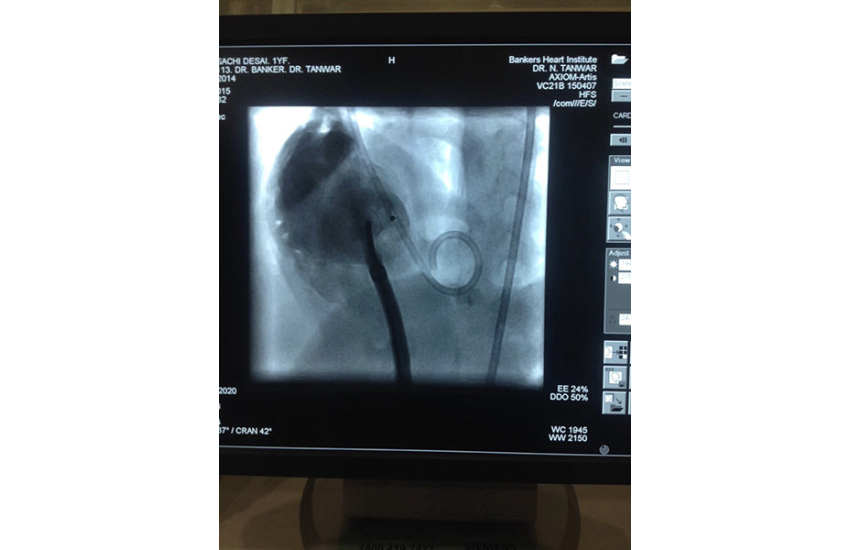

Some people have a habit of turning, playing or twiddling with their pacemakers. This can cause leads of the pacemaker to be pulled out. In the first 2 pictures, the leads can easily be seen circling the pacemaker, a sure sign of being twiddled with.

Our team went ahead to correct this problem and educate the patient about leaving their pacemaker.